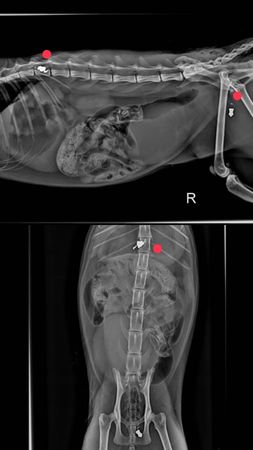

▲彰化小貓咪身中2彈傷重不治。(圖/民眾提供)

民眾po網臉書「社頭人俱樂部」,指出4月28日深夜9點40分在舊社國小附近福德路上有一隻貓咪躺在路中間,緊急送醫院。經醫師檢查,醫生說貓咪是惡意被攻擊,身體裡卡著兩個鉛彈,很危急。

民眾說,貓咪有剪耳,有被被帶去結紮在原地放回,應該是很親人,以傷口來看,明顯像是近距離攻擊,甚至是刻意射擊脊椎與下腹部,以身上的傷勢來看也不是第一時間了,貓咪躺在那受苦已經有一段時間。最後在手術中,貓咪仍舊因為傷重不治。